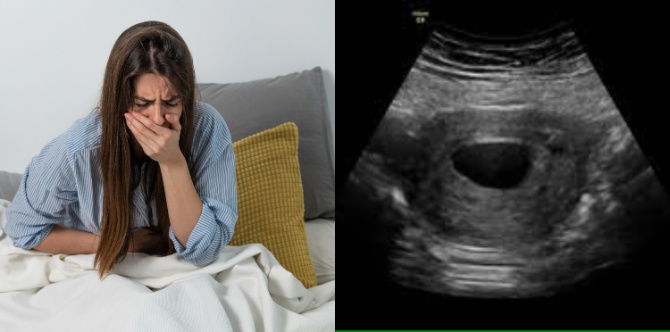

Ujian kehamilan yang paling biasa dilakukan menggunakan air kencing untuk mengesan hormon hCG. Ujian darah juga boleh digunakan untuk mengesahkan kehamilan lebih awal dan memberikan maklumat yang lebih terperinci tentang keadaan kesihatan ibu dan janin.